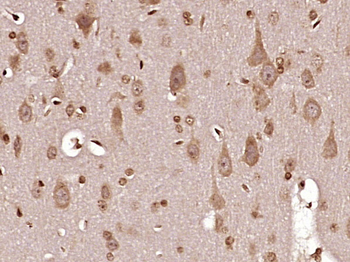

FC, IF, IHC-Fr, IHC-P

应用稀释比例:IHC-P=1:100-500, IHC-F=1:100-500, IF=1:100-500, Flow-Cyt=1ug/Test